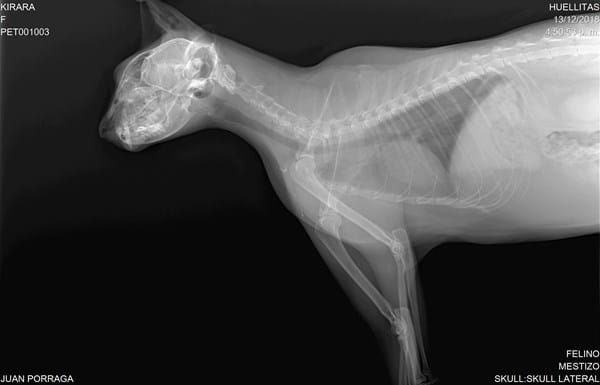

Mi gata de 4 años, castrada, presenta ruidos al respirar (no es permanente solo en ocasiones) donde parece pujar o generar silbidos (sobre todo al ronronear). También presenta estornudos ocasionales, ronquidos en raras ocasiones y tos muy de vez en cuando. Se le ha realizado una radiografía de tórax y demás y sale en completa normalidad (pulmones y vías respiratorias), la veterinaria dice que puede ser por estar un poquito pasada de peso, pero los ruidos continúan y me siento preocupado.